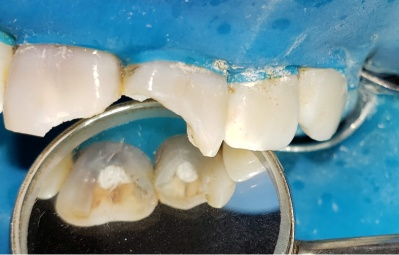

Obturación y blindaje coronario inmediato

Se utilizaron conos de gutapercha con taper 06 y calibre 35 (Meta-Biomed)(Fig14-15), desinfectados con alcohol al 70%, con técnica de condensación lateral y sellador AH Plus (Dentsply-Sirona)(Fig.15-16-17) . Se realizó un blindaje coronario inmediato con composite (Fig.19) y teflón estéril (Fig.18). Este blindaje no solo protege la obturación de una posible reinfección, sino que sella mecánicamente la cavidad ante posibles filtraciones (Ricucci et al., 2022). Además, forma parte de la tendencia actual en endodoncia restauradora que aboga por realizar reconstrucciones postendodónticas el mismo día siempre que sea posible.

En este caso, debido al cansancio manifestado por la paciente tras la extensa y compleja sesión clínica, se decidió programar la colocación de los postes de fibra de vidrio a los 7 días.

Fig 16 Condensación lateral a conos múltiples

Fig. 17 Corte de conos

Fig. 18 Blindaje con teflón estéril

Fig. 19 Blindaje con composite vista palatina

Fig. 20 Blindaje coronario y reconstrucción provisoria estética